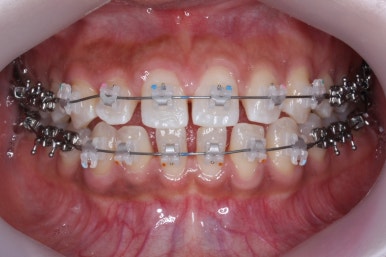

위 사진은 부산치아교정치과에 내원하셨을 대 당시의 입안 모습입니다.

치아들 사이에 전반적으로 틈이 많이 있는 상태입니다.

장치 부착 모습입니다.

이번에 부산치아교정치과에서 사용한 장치는 클리피씨라는 자가결찰 세라믹입니다.